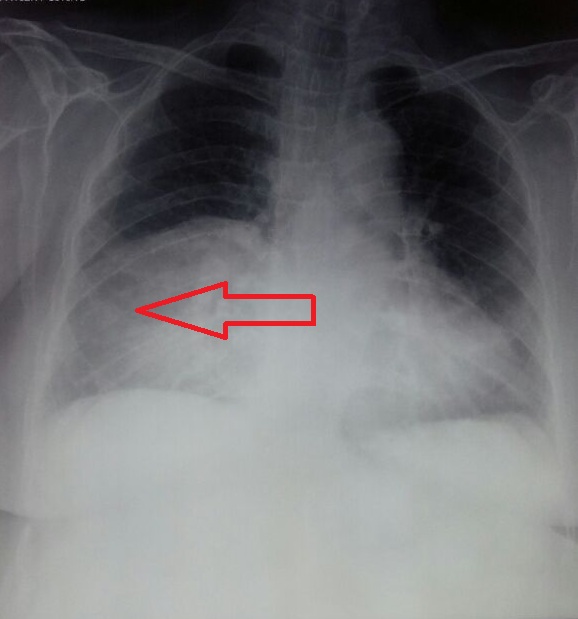

Eight decades of asymptomatic Morgagni Hernia

Morgagni hernia, diaphragmatic hernia, congenital herniaAbstract